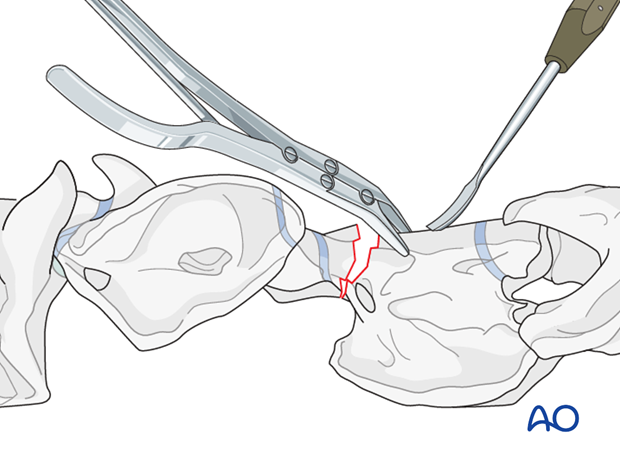

This procedure is performed with the patient positioned in dorsal recumbency through the ventral midline approach to the cervical spine.

The ventral spinous process of the body of C2 is flattened slightly using a curved osteotome and bone rongeur.

After exposing the ventral surfaces of the atlas and axis, the alignment of the vertebrae is corrected and maintained with bone-holding forceps.